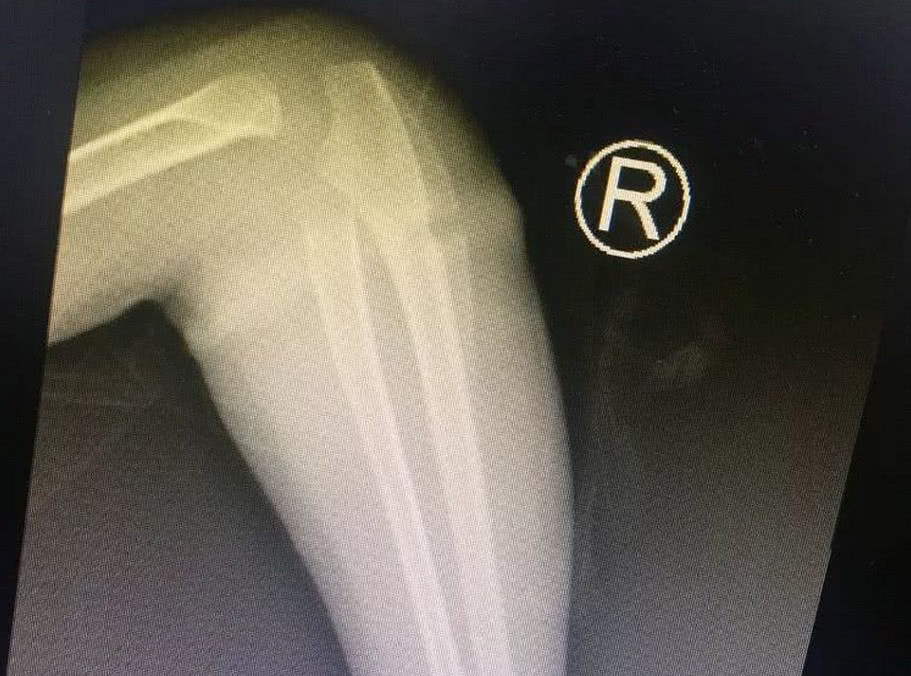

经过B超检查,牛主任说女儿的手臂里面有一条橡皮筋,因为时间太长已经长到了肉里面去了,如果在不治疗的话,就会截肢,听到这话后,小丽和老公看了看一旁的婆婆,都后悔不已,觉得不应该把女儿交给婆婆照顾的。如果自己带的话就不会发生这样的事情。

有了明确的诊断,牛主任开始为乐乐手术。这个手术并不难,无影灯下,历经半小时就将“圆环”擒拿归案,把长在肉里的环形橡皮筋取了出来,彻底解决了乐乐的病痛。